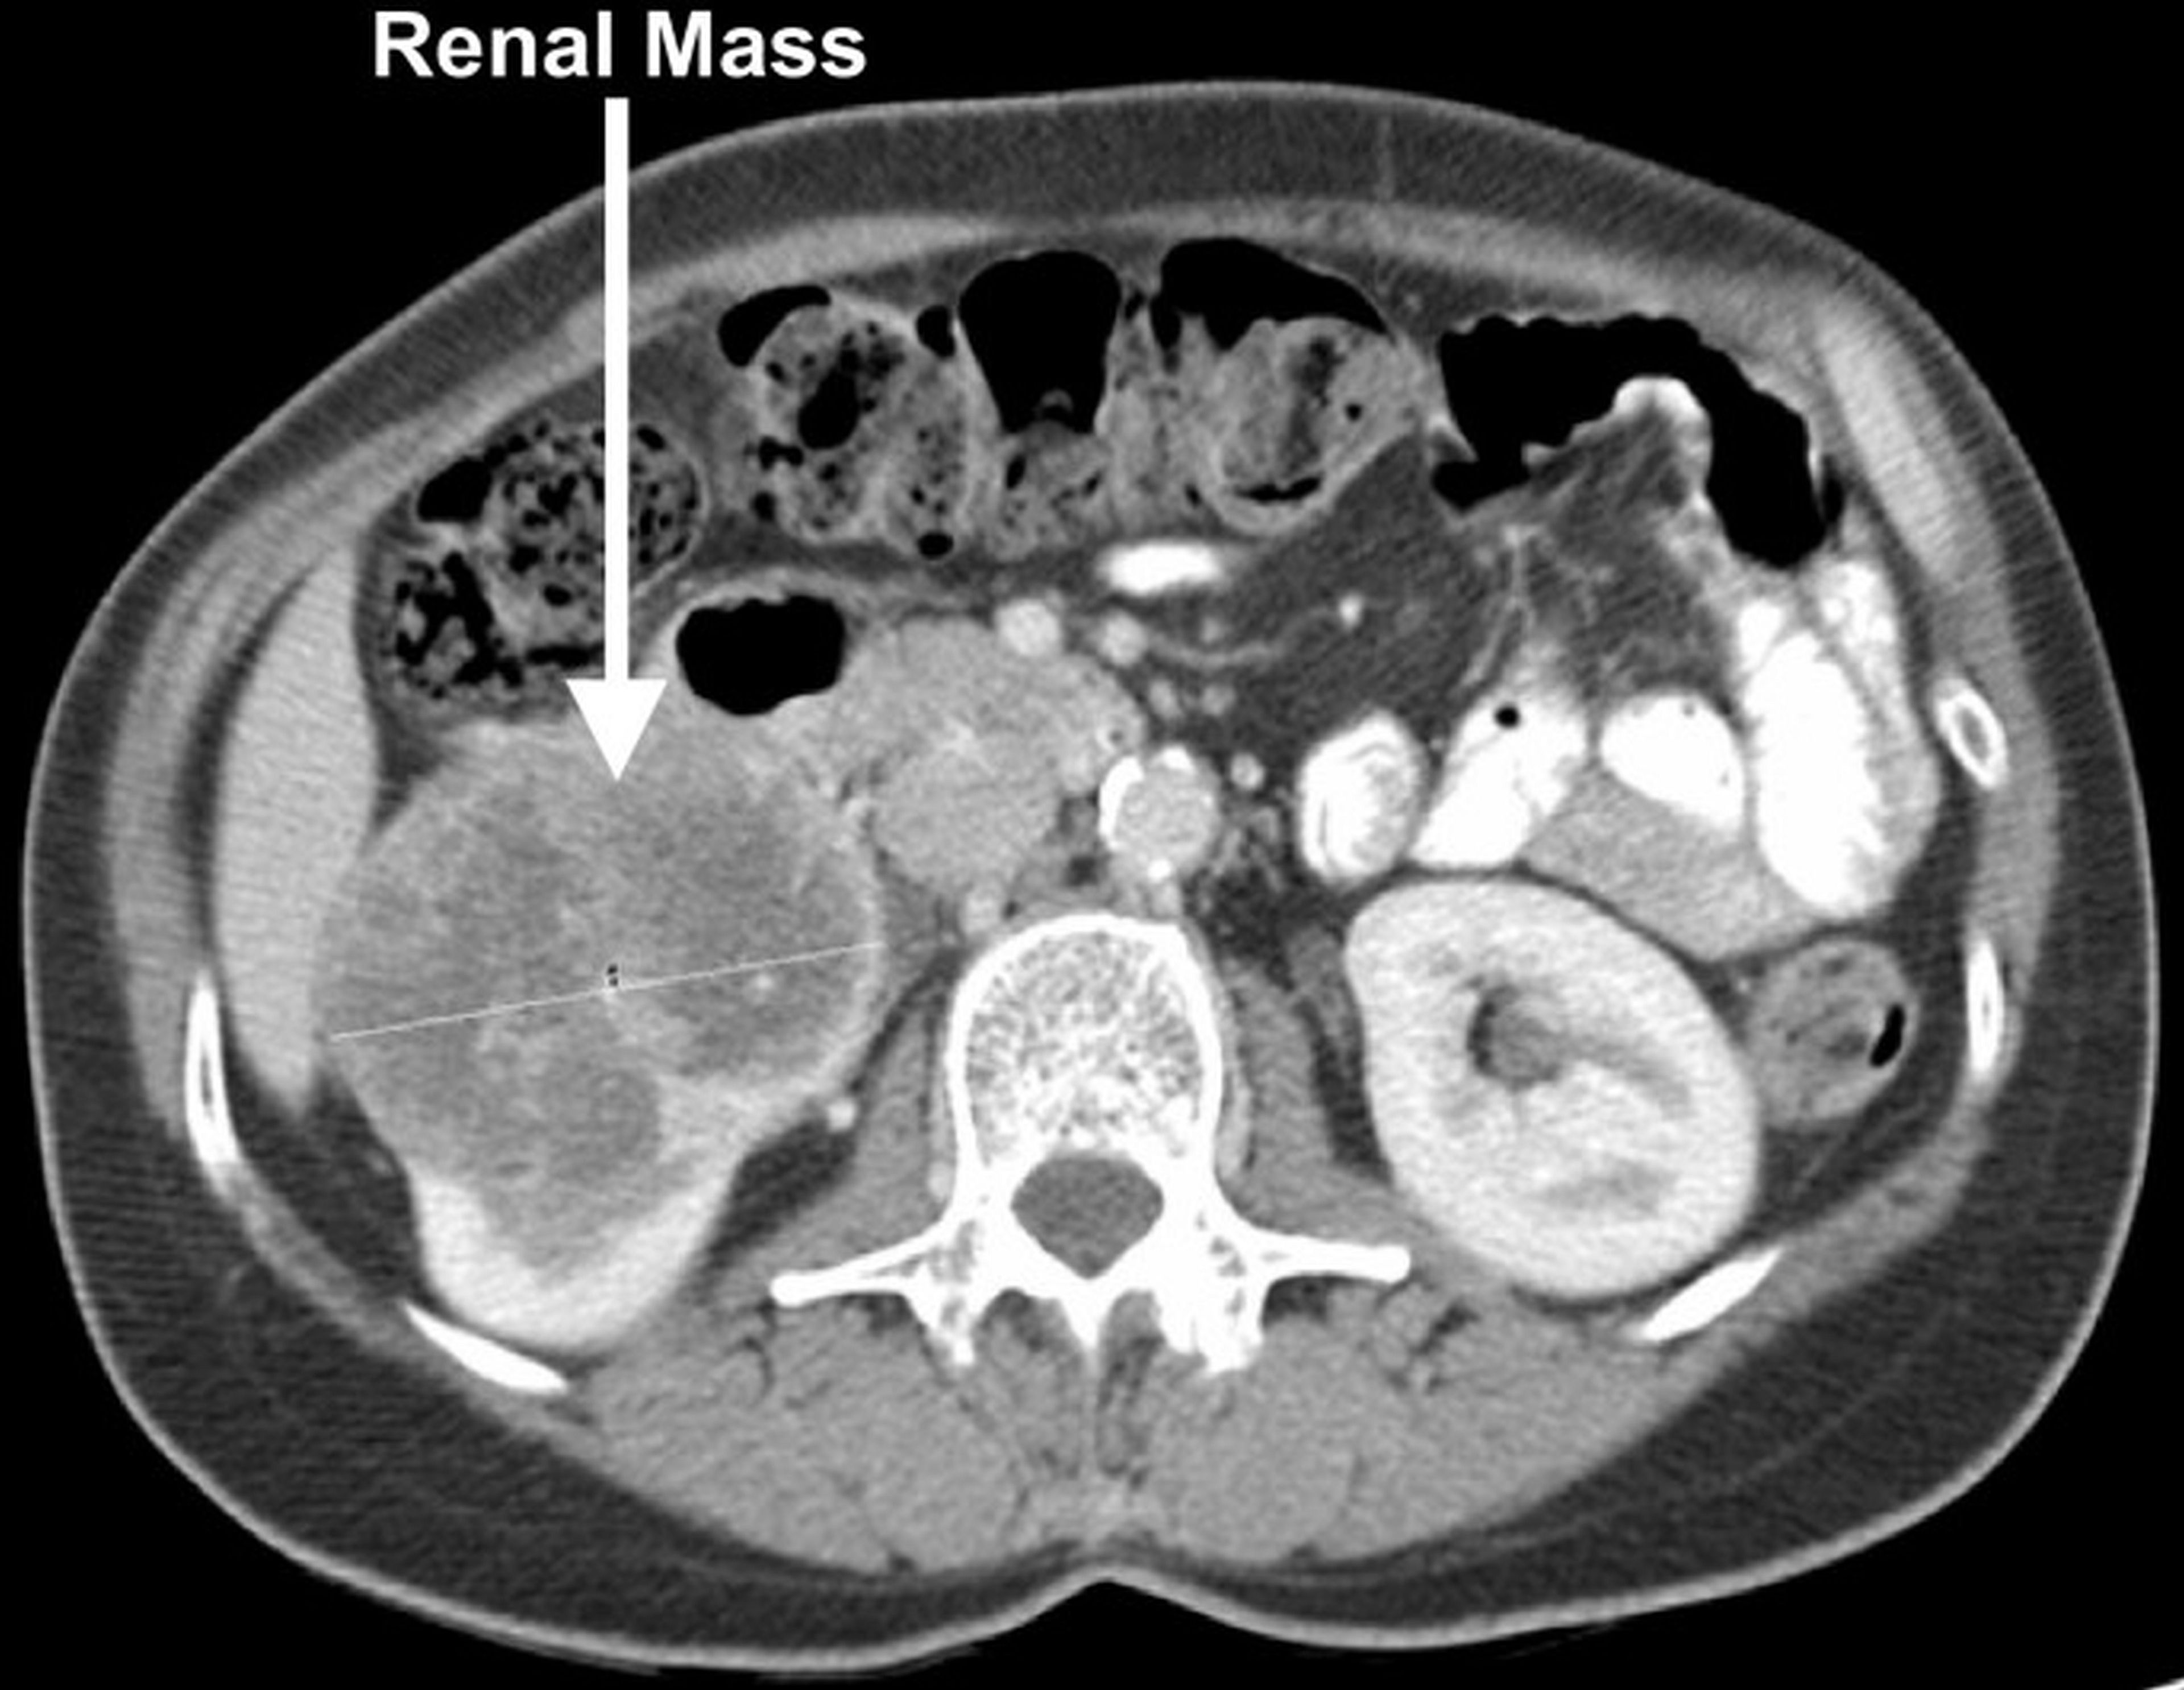

There are several types of cancer that can affect the kidneys. Renal cell carcinoma (RCC), is the most common form and accounts for approximately 85% of all kidney cancers. In RCC, malignant cells develop in the lining of the kidney's tubules and typically grow into a mass called a tumour. The earlier kidney tumours are discovered, the better a patient's chances for survival. Tumours discovered at an early stage often respond well to treatment. Survival rates in such cases are high. Tumours that have grown large or spread to other parts of the body are much more difficult to treat and present a greatly increased risk to patients life.

Patients who have loin pain, blood in urine or a vagulely felt lump in upper abdomen are likely to have kidney cancer. It is important to consult a nearby doctor to get ultrasound scan followed by a specialist consultation to decide on further course of action.